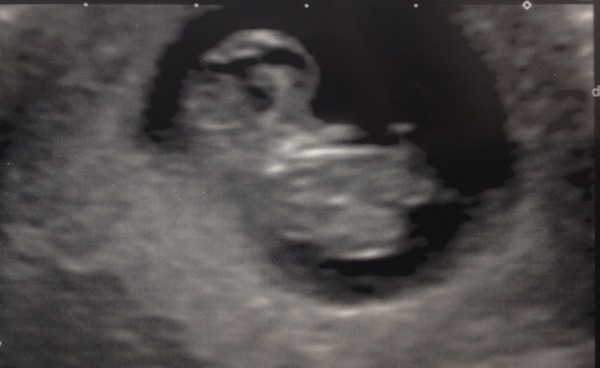

Here is little bean! Looks more baby shaped than I thought at this stage :)

July thread - we are nearing the end of the first trimester, announcements will be made soon!